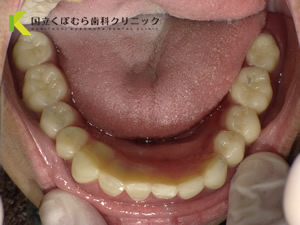

下額:左下3 2 マグネット 右下1 2 3 コーヌス支台 をしてコーヌスマグネットデンチャーで修復

費用:上顎54万円 下額76万円

期間:10か月

治療のリスク:状態によっては施術できないこともあります。場合によっては腫れや痛みが発生することがあります。